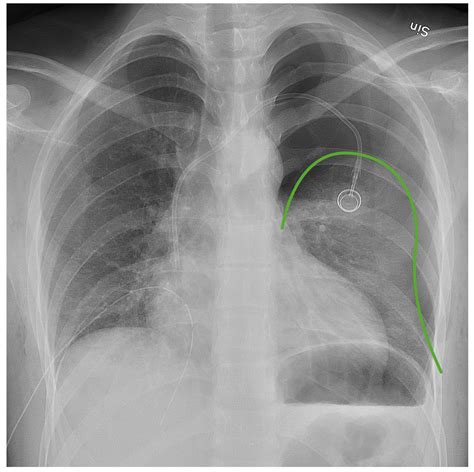

Tension Pneumothorax

A tension pneumothorax is a medical emergency where air continues to accumulate in the pleural space, leading to increased pressure and potential collapse of the lung and mediastinal shift. On an X-ray, it shows a large area of hyperlucency with a deviated mediastinum and flattened diaphragm on the affected side.

5. Examine the Mediastinum: Check for any deviation of the mediastinum towards the unaffected side, which may indicate a tension pneumothorax.

• Chest Tube Insertion: In cases of tension pneumothorax or persistent pneumothorax, a chest tube may be inserted to continuously drain the air and allow the lung to re-expand.